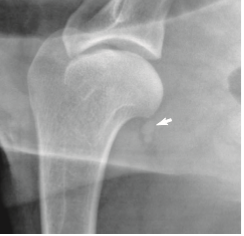

What arteries supply the head and neck of the femors?

The medial and lateral deep circumflex artery from the sacral (70%)

Gluteal arteries (30%)